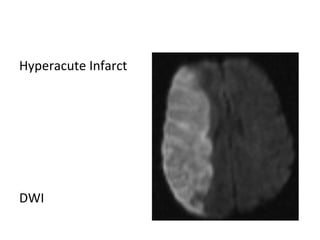

a) Hyperacute Infarct (0-6 hours)

a) Hyperacute Infarct (0-6 hours) :

-Within minutes of critical ischemia , the sodium-

potassium ATPase pump that maintains the normal

low intracellular sodium concentration fails , sodium

& water diffuse into cells leading to cell swelling and

cytotoxic edema

-Calcium also diffuses into cells which triggers cascades

that contribute to cell lysis

-Diffusion is the most sensitive modality , DWI

hyperintensity & ADC map hypointensity reflect

reduced diffusivity which can be seen within minutes

of the ictus

-Diffusion is reduced in acute infarct by 2 factors:

1-Shift from extracellular to intracellular water due to

Na/K ATPase pump failure

2-Increased viscosity of infarcted brain due to cell lysis

and increased extracellular protein

-FLAIR may be normal , subtle hyperintensity may be

seen on FLAIR

-Perfusion shows decreased cerebral blood volume of

the infarct core with or without a surrounding region

of decreased cerebral blood flow which represents

the penumbra

Hyperacute Infarct

T1

T2

Flair

DWI

ADC